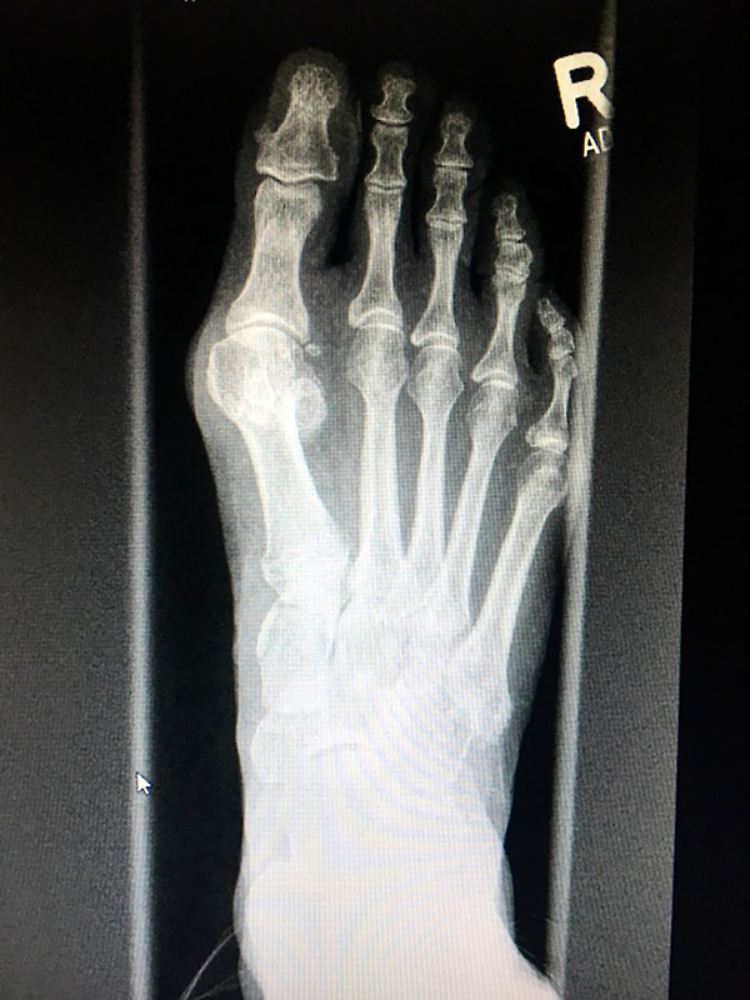

Bei diesem Fuß wurde die schiefstehende Großzehe mittels einer "Open Wedge Osteotomie" korrigiert. Dabei wird der Fuß verschmälert und unter anderem eine Titanplatte mit Abstandhalter verschraubt, die später wieder entfernt wird. Ziel ist, dass die große Zehe am Ende von allein gerade steht.

(Foto: dpa)